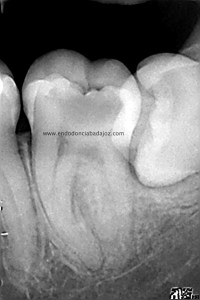

Se trata de un caso que ,a priori, traté como un 3.7 de tres conductos:

Después de haber instrumentado con un sistema Protaper, y habiendo estandarizado el conducto en un 25mm en apical y una conicidad del 6% con limas K3. observé que el conducto Distal presentaba otro conducto Disto-Vestibular cuya entrada estaba en la pared del conducto Disto-Lingual tratado, bastante complicado de trabajar.

Observando la Rx pude verificar y diferenciar las raices: